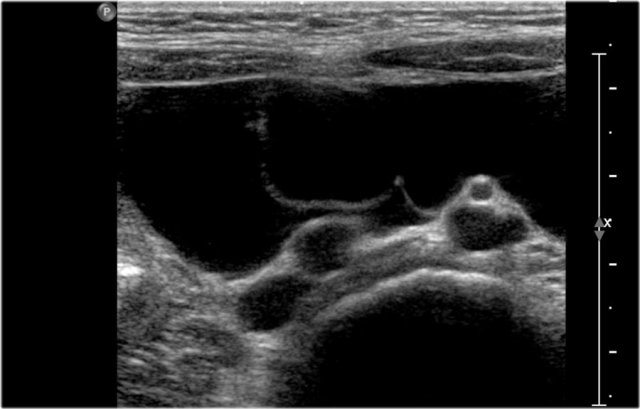

The image is of a one-month-old boy with a MCKD on prenatal ultrasound.

Some tissue and several large cysts are seen.

On Tc-99-DMSA scintigraphy no uptake was seen on the left side.

This is compatible with a MCKD.